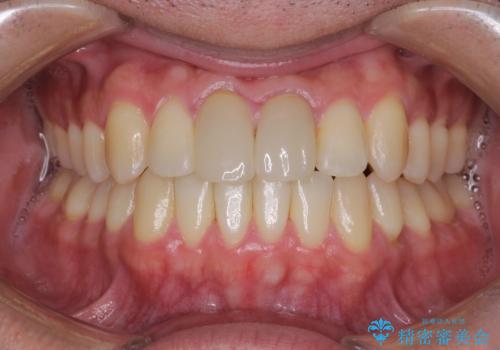

上下のがたつきをインビザラインで目立たない矯正

- 前歯のガタガタを主訴に来院されました。

上下の前歯のガタガタと左上の歯が反対にかんでいる状態でした。

上下の歯と歯の間をわずかに削り並べる計画としました。

目立たずに歯並びがよくなり、前歯に装着されたセラミックも壊さずに矯正治療が終了し満足していただけました。